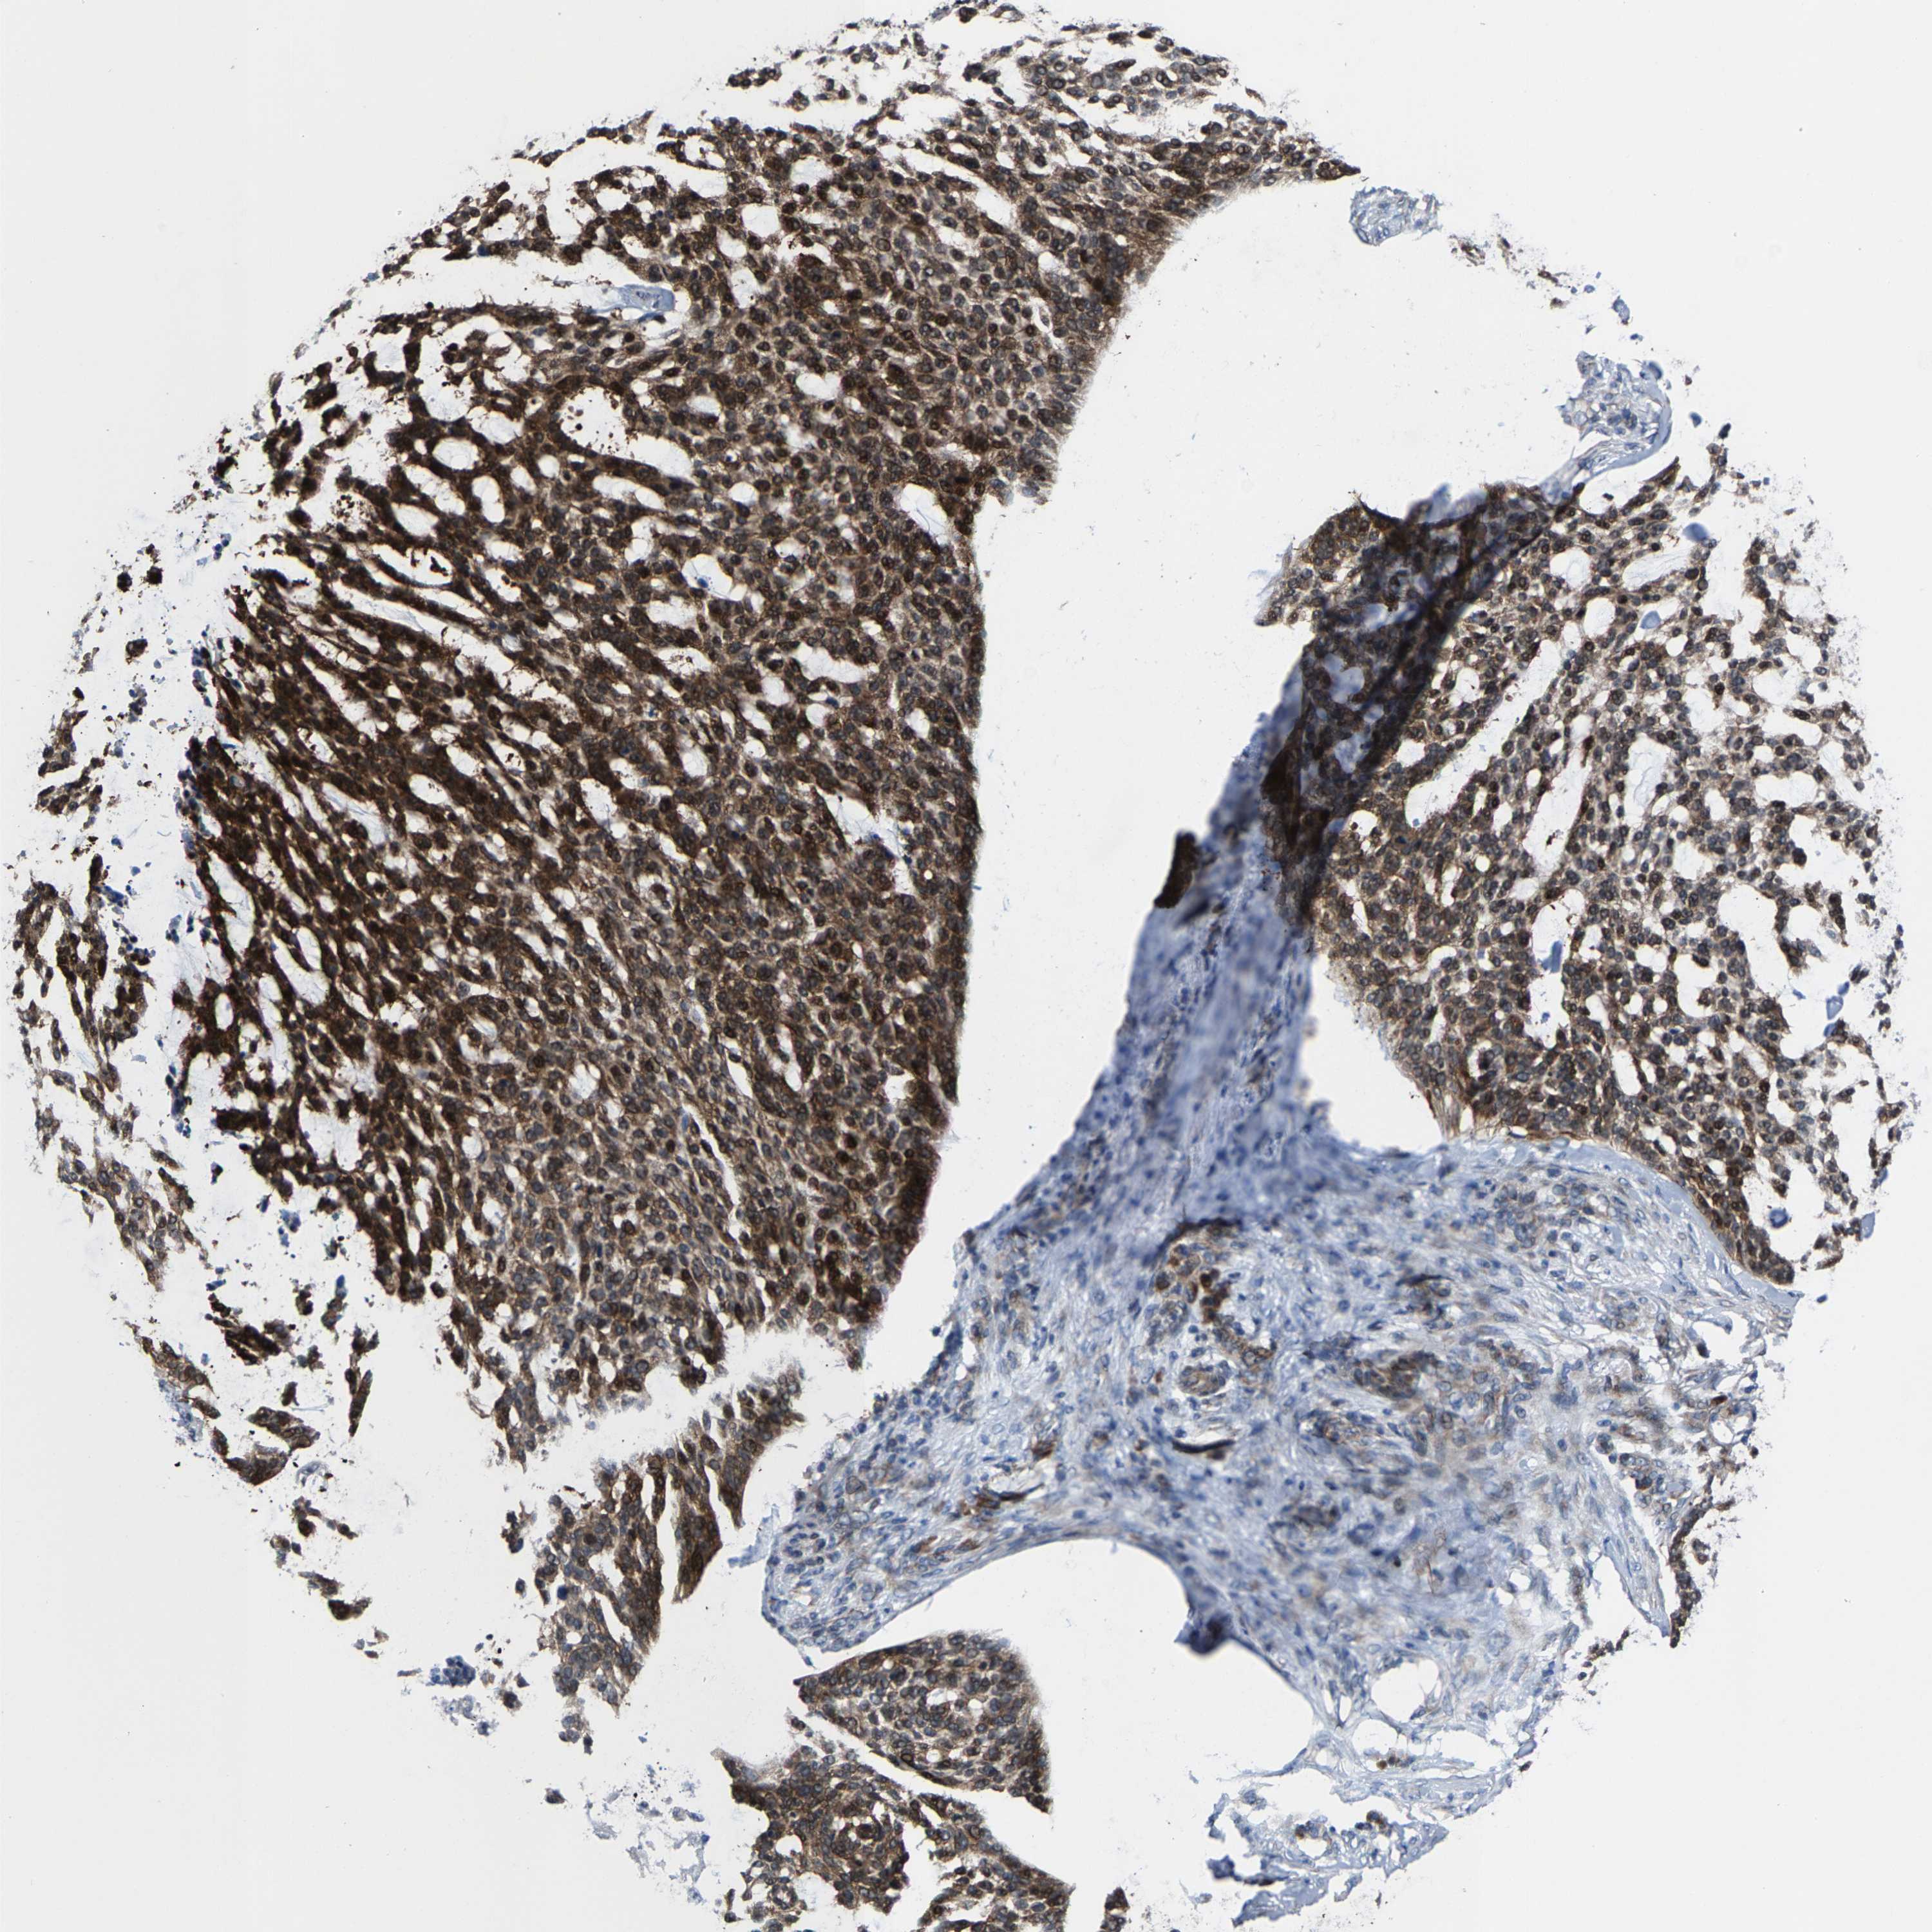

Basal cell and squamous cell cancer

SKIN CANCER - Protein expressioni

A mouse-over function shows sample information and annotation data. Click on an image to view it in a full screen mode. Samples can be filtered based on level of antibody staining by selecting one or several of the following categories: high, medium, low and not detected. The assay and annotation is described here.

Antibody stainingi

Antibody staining in the annotated cell types in the current human tissue is reported as not detected, low, medium, or high, based on conventional immunohistochemistry profiling in selected tissues. This score is based on the combination of the staining intensity and fraction of stained cells.

Each image is clickable and will lead to virtual microscopy that enables deeper exploration of all samples and also displays staining intensity scores, fraction scores and subcellular localization as well as patient and tissue information for each sample.

Antibody HPA020960

Antibody HPA020965

Staining

High

Medium

Low

Not detected

Intensity

Strong

Moderate

Weak

Negative

Quantity

>75%

75%-25%

<25%

None

Location

Nuclear

Cytoplasmic/membranous

Cytoplasmic/membranous,nuclear

Basal cell carcinoma

Squamous cell carcinoma, NOS

Squamous cell carcinoma, metastatic, NOS